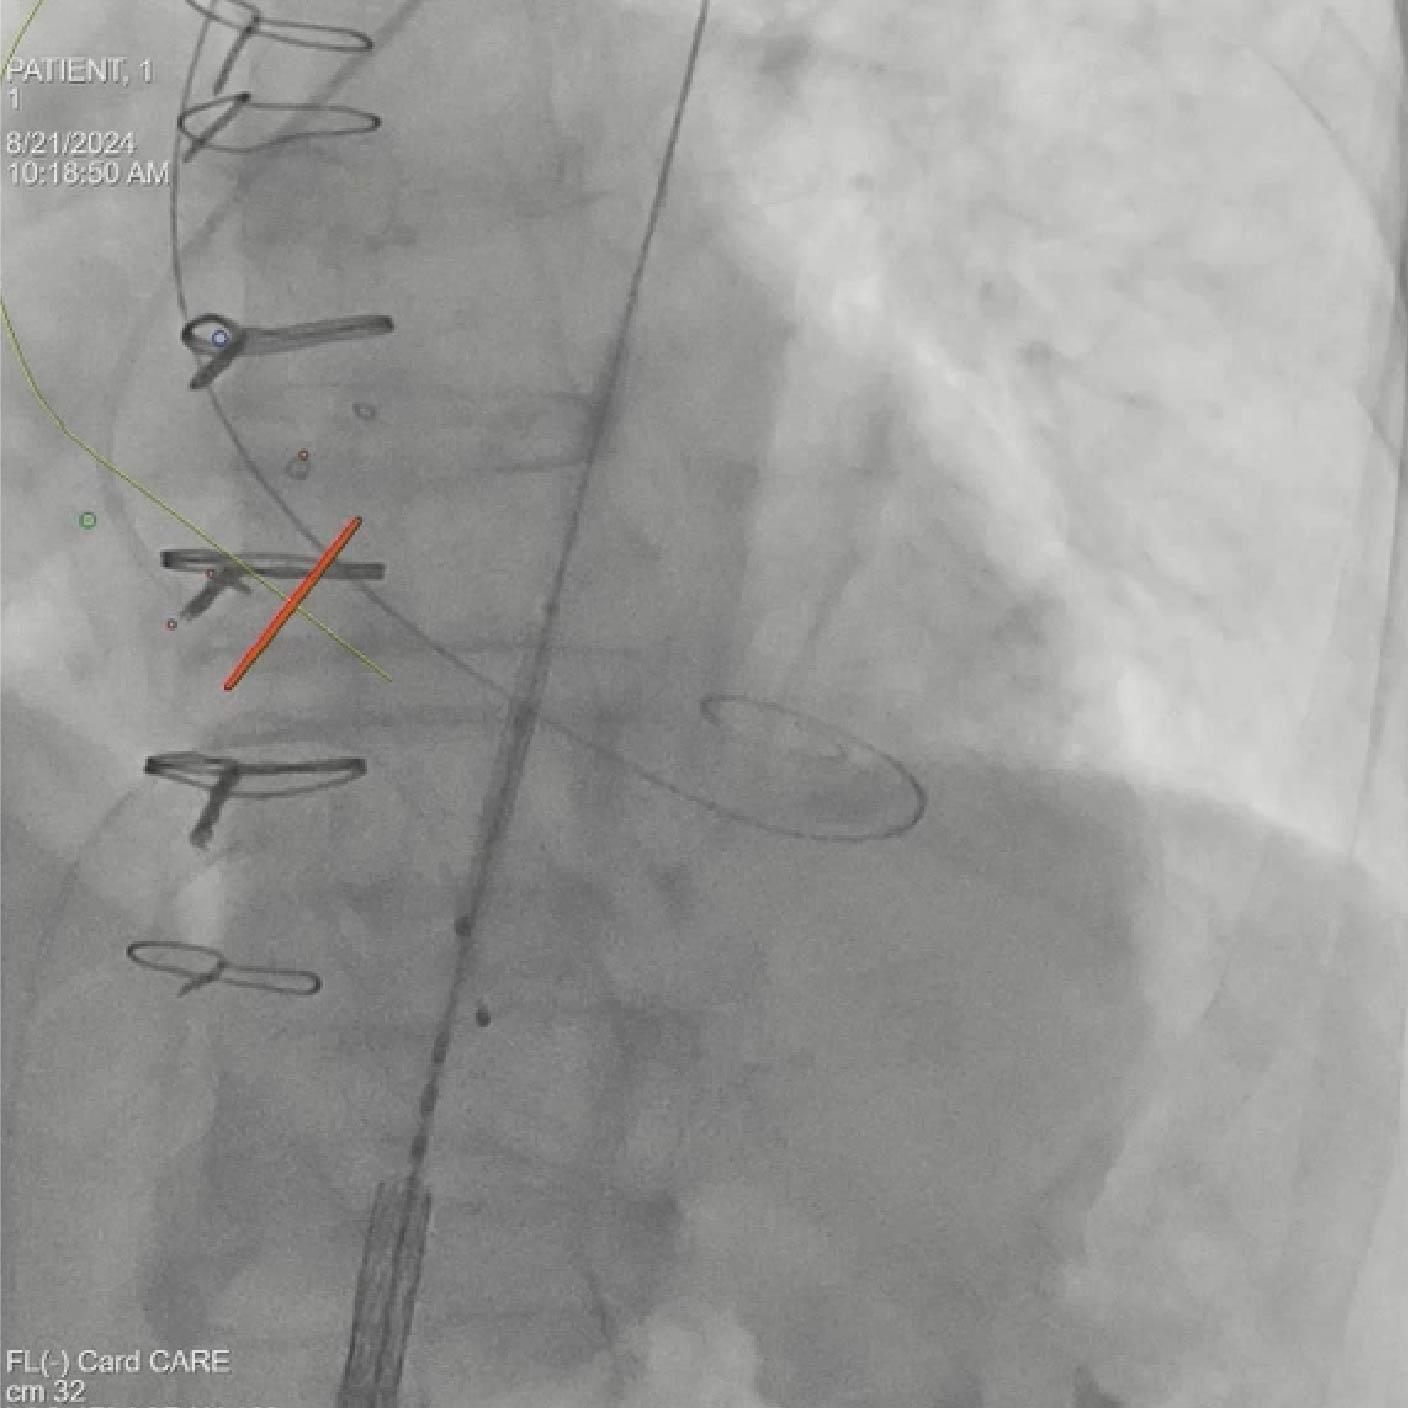

- Colocación del guía y del dispositivo con syngo Aortic Valve Guidance

Soluciones y características seleccionadas: ARTIS pheno, Case Flows, Una combinación preestablecida de configuraciones (angulación, disposición de la pantalla, etc.), personalizada para la colocación del dispositivo SENTINEL™*, reduce las interacciones con el sistema. Con Case Flows, una única interacción del usuario reemplaza el ajuste de hasta 6 configuraciones del sistema³. syngo 2D/3D Fusion - Aplicación para superponer la anatomía de la arco aórtico basada en tomografía computarizada sobre fluoroscopia en vivo, para apoyar la navegación del dispositivo. Se ha demostrado que la guía por fusión reduce significativamente el tiempo de despliegue del dispositivo SENTINEL™* y el uso de contraste⁴.

Soluciones y características seleccionadas: 3mensio (Pie Medical Imaging) Software semiautomatizado para asistir en la reconstrucción 3D de la válvula previamente implantada y la anatomía circundante, con el fin de determinar el abordaje ideal y el tamaño adecuado de la válvula. Su uso reduce el tiempo de planificación del TAVR¹ y los resultados de la planificación pueden exportarse para superposición en tiempo real durante la fluoroscopia.